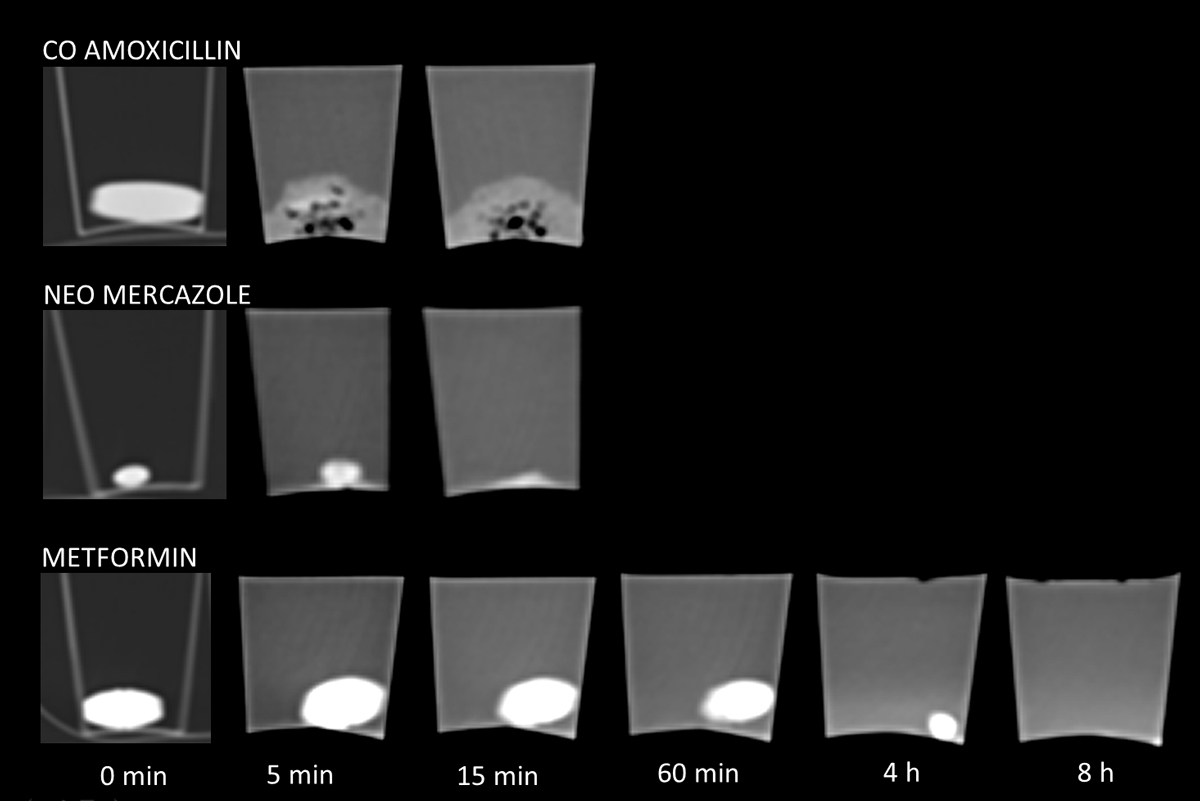

The HU and CT spectroscopy values are valid only as long as the pills are not dissolved (in hydrochloric acid). In addition to disintegration of the HU, a dissolving pill had blurred margins and loss of shape and contour (fig. 5). Each pill’s individual duration of integrity is marked in green in table S1 (appendix 1, available in a separate file for downloading); the red fields indicate the time when the pills were first dissolved. Twenty-one medicaments had already dissolved after 5 minutes in hydrochloric acid and another 10 after 30 minutes; 11 pills were intact for 2 hours or longer (up to 4 days, table S1). HU values from both scans at 100 kVp (table S2) and 120 kVp are reported for the entire duration of the experiment, since CT spectroscopy of pill sedimentation can theoretically still be used after decomposition (in a laboratory environment and without bowel movements).

Figure 5 Dissolution process of medicaments in hydrochloric acid (pH 2): Co-Amoxicillin was already dissolved after 5 min (note the small black air bubbles during the decay). Neo Mecazole was still intact after 5 min and dissolved after 15 min. Metformin demonstrated the same shape and density over 60 min and was dissolving after 4 hours. Note the hyperdense liquid in the cup at 8 hours.